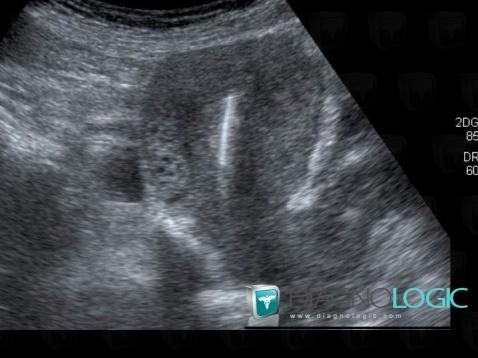

Intrauterine device, Uterus, US

Here is the specific information in the key image above:

- Diagnosis Intrauterine device, Location(s) Uterus, with gamuts